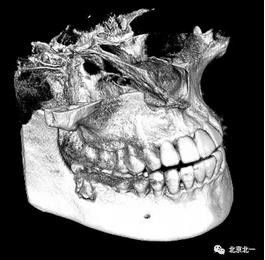

圖四:三維重建

圖五:三維重建可見牙冠突破舌側